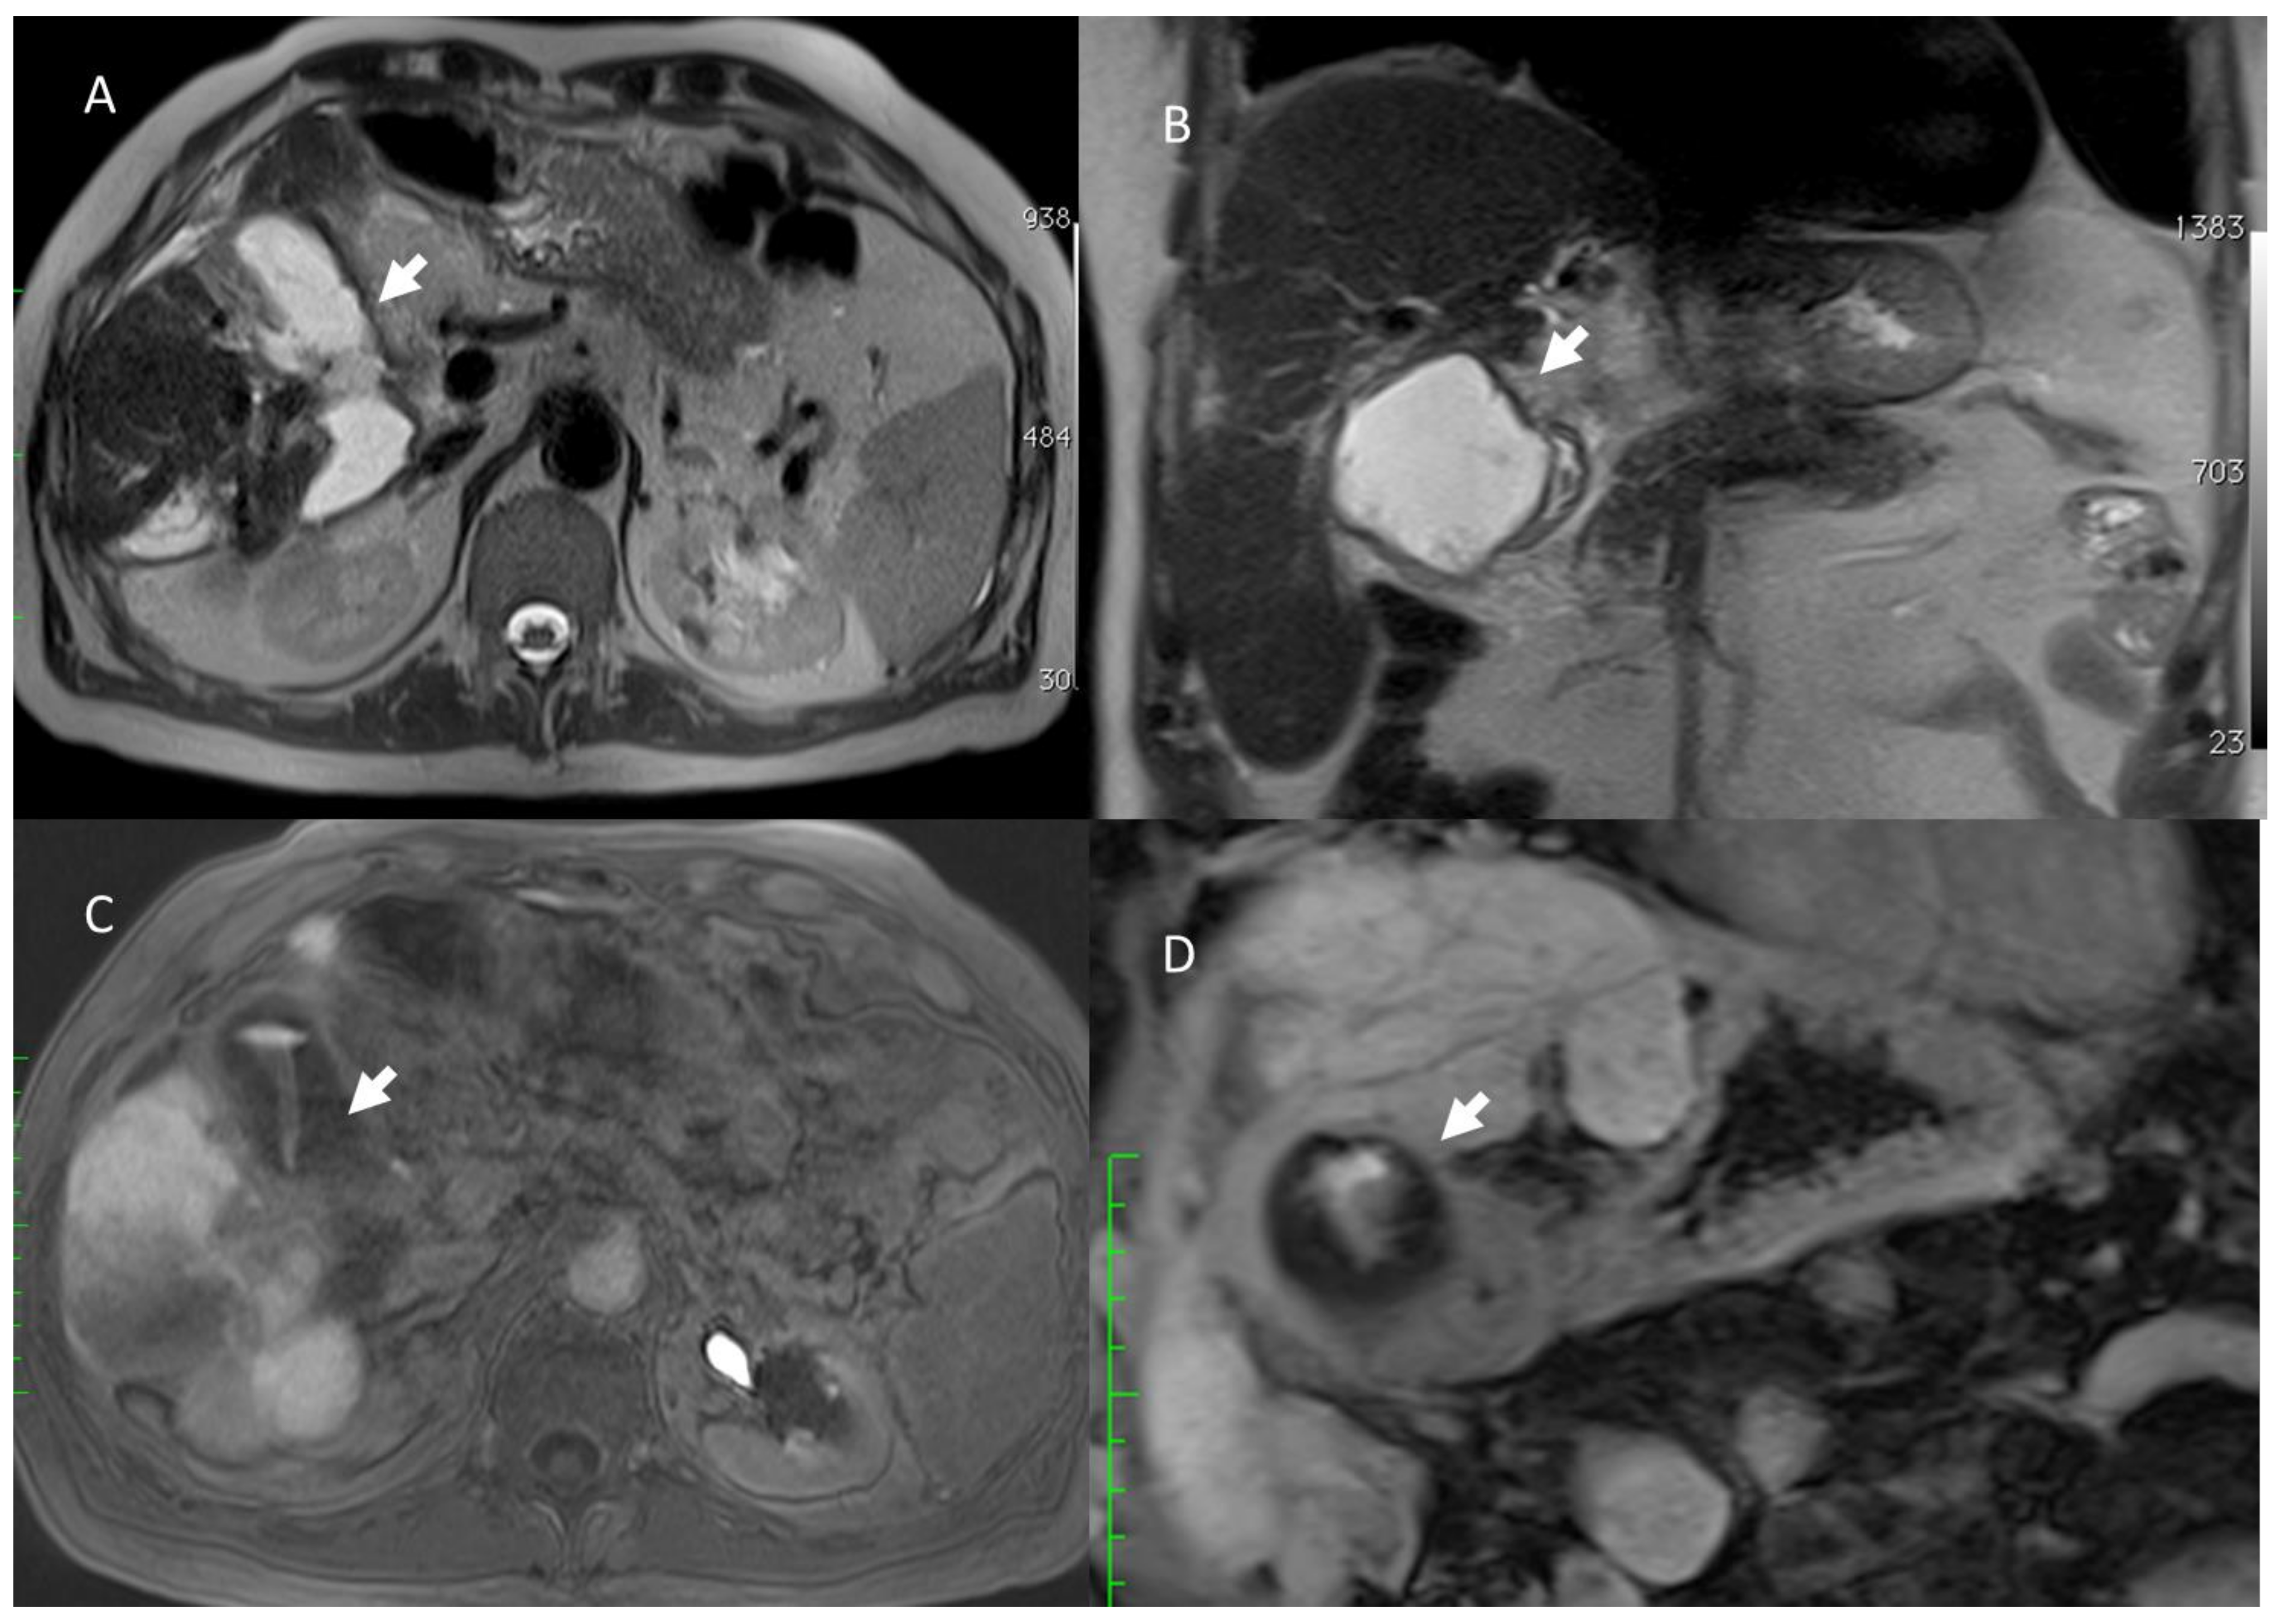

- Granata, V.; Grassi, R.; Fusco, R.; Setola, S.; Belli, A.; Piccirillo, M.; Pradella, S.; Giordano, M.; Cappabianca, S.; Brunese, L.; et al. Abbreviated MRI Protocol for the Assessment of Ablated Area in HCC Patients. Int. J. Environ. Res. Public Health 2021, 18, 3598. [Google Scholar] [CrossRef]

- Granata, V.; Grassi, R.; Fusco, R.; Setola, S.V.; Belli, A.; Ottaiano, A.; Nasti, G.; La Porta, M.; Danti, G.; Cappabianca, S.; et al. Intrahepatic cholangiocarcinoma and its differential diagnosis at MRI: How radiologist should assess MR features. Radiol. Med. 2021, 126, 1584–1600. [Google Scholar] [CrossRef]

- Granata, V.; Grassi, R.; Fusco, R.; Belli, A.; Cutolo, C.; Pradella, S.; Grazzini, G.; La Porta, M.; Brunese, M.C.; De Muzio, F.; et al. Diagnostic evaluation and ablation treatments assessment in hepatocellular carcinoma. Infect. Agents Cancer 2021, 16, 53. [Google Scholar] [CrossRef] [PubMed]

- Izzo, F.; Granata, V.; Grassi, R.; Fusco, R.; Palaia, R.; Delrio, P.; Carrafiello, G.; Azoulay, D.; Petrillo, A.; Curley, S.A. Radiofrequency Ablation and Microwave Ablation in Liver Tumors: An Update. Oncologist 2019, 24, e990–e1005. [Google Scholar] [CrossRef] [Green Version]